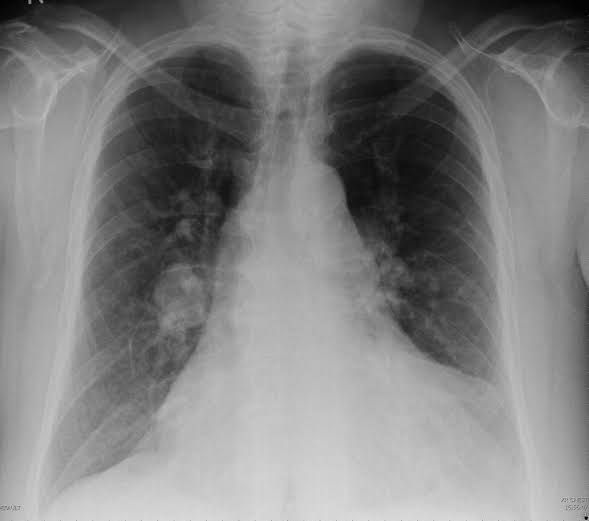

The Fleischner sign refers to a prominent central pulmonary artery that can be commonly caused either by pulmonary hypertension or by distension of the vessel by a large pulmonary embolus. It can be seen on chest radiographs, CT pulmonary angiography (CTPA), and MR pulmonary angiography (MRPA). It is seen most commonly in the setting of massive pulmonary embolism (defined angiographically as involving 50% or more of the major pulmonary artery branches). It has a low sensitivity but high specificity. It is one of several described signs of pulmonary embolus on chest radiographs.